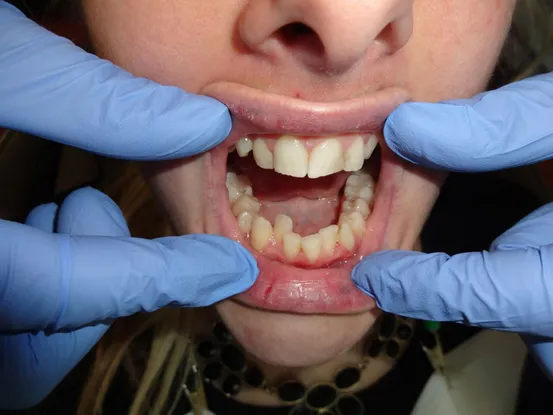

Case 1

26 year old female with teeth crowding and slight overbite. Patient refused to have 2 years of orthodontics. Gingivectomy, cosmetic bonding, extraction, Zoom Bleaching, and 12 units of e-max restorations performed.